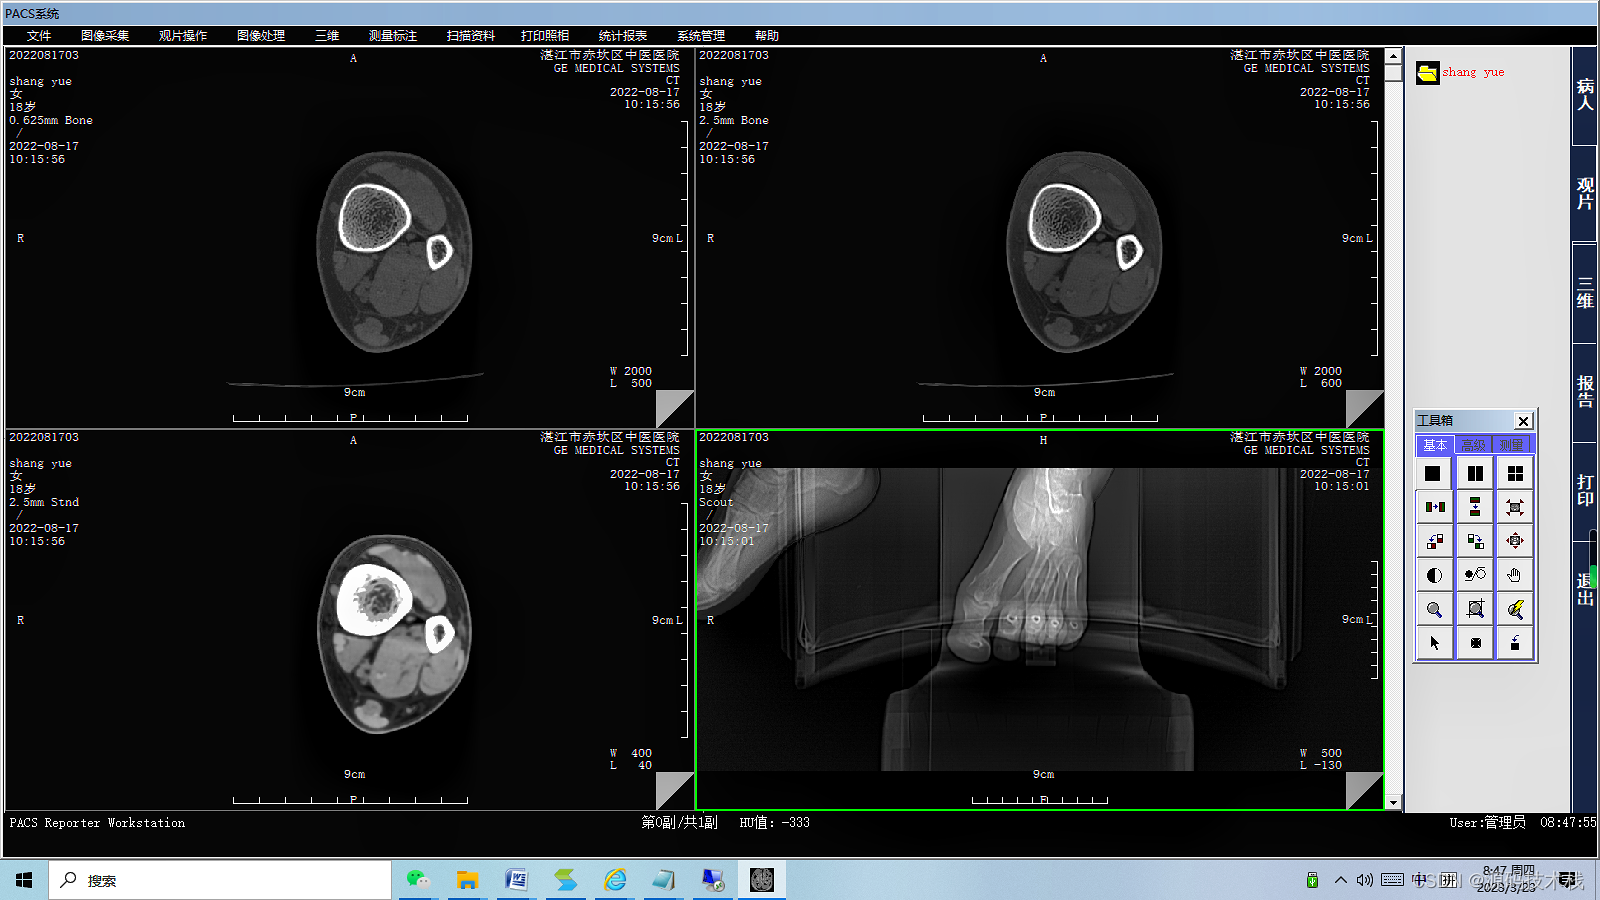

PACS是Picture Archiving and Communication Systems首字母缩写,全称为影像储存和传输系统,涉及放射医学、计算机技术、通讯技术及数字图像技术等,是医院信息系统的重要组成部分,是将数字医疗设备(如X线、CT、MRI、超声、病理等)所产生的医疗图像进行获取、储存、管理、诊断及信息处理的重要系统。PACS集医疗图像获取、数据储存、图像的显示和处理、数据管理及传输影像等技术为一体,大大降低了医生对传统硬拷贝技术的依赖。

PACS主要包括图像获取、图像传输、图像储存和管理、图像影像工作站进行阅读四个流程。临床上,PACS系统流程从患者在登记台登记检查开始,然后患者进入检查室,技师进行检查,采集影像数据,将采集的影像数据进行上传至PACS网,影像医师通过PACS调阅图像并书写报告,最后将PACS的图文报告归档。

PACS改变了传统图像保存和传递方式,成本低,保存时间长,方便图像的存取,使影像医师和临床医师能够随时读取影像资料。